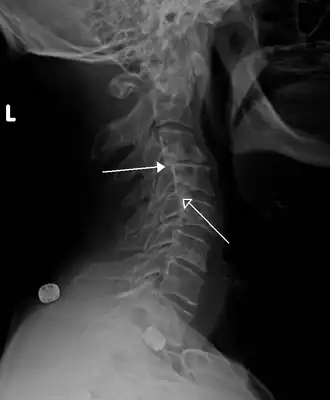

Imagen de rayos X de una anterolistesis ístmica de grado 1 en L4-5 -

Anterolistesis L5/S1. Flecha azul pars interarticularis normal. La flecha roja es una ruptura en pars interarticularis -